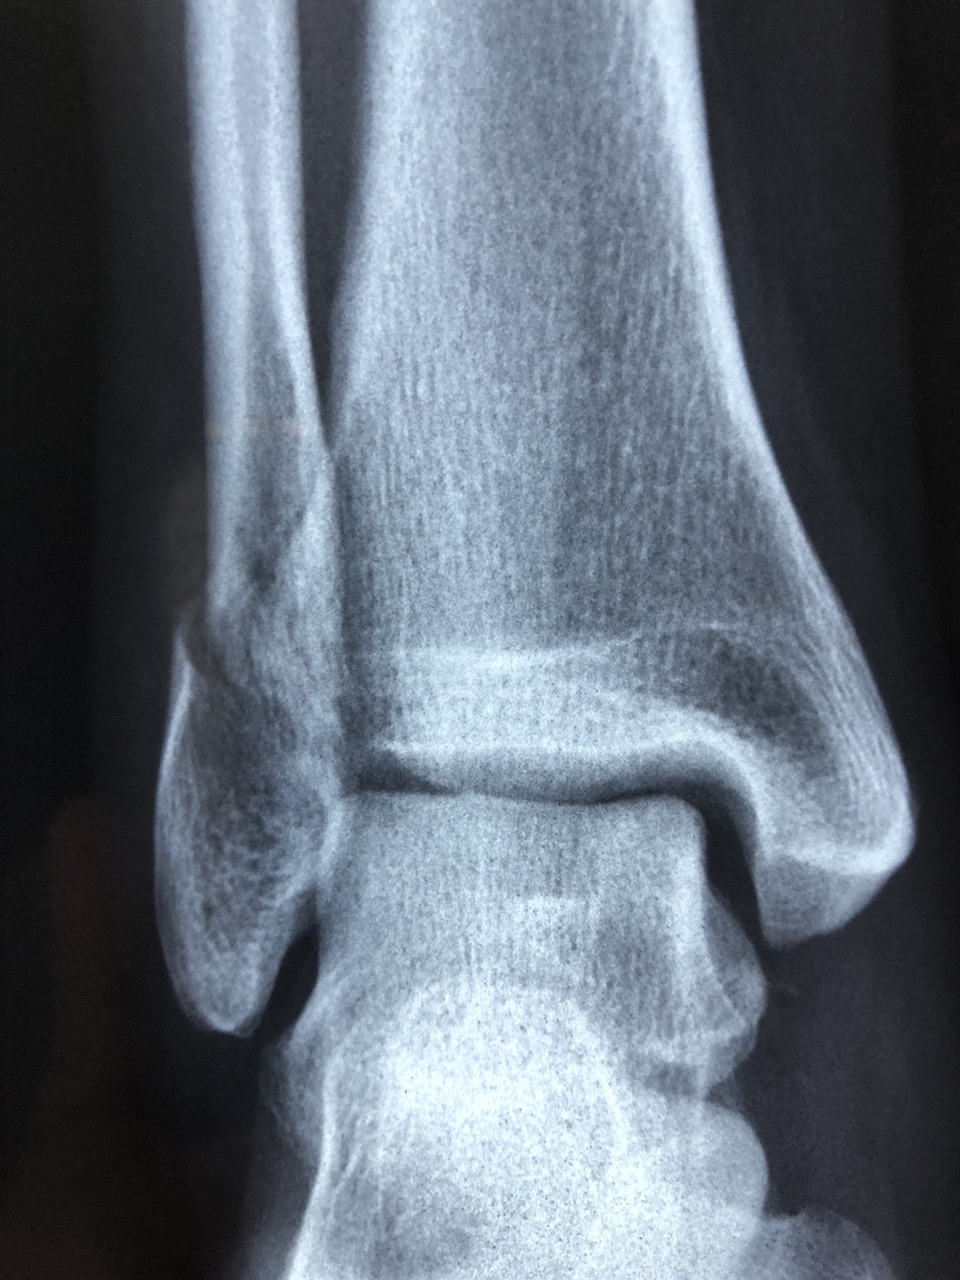

염좌와 탈구의 진단 방법

염좌와 탈구를 진단하는 데 있어 가장 중요한 단계는 전문 의료진의 신체 검진입니다. 염좌의 경우 관절의 움직임과 부종 정도를 평가하며, 필요에 따라 X-ray를 촬영해 골절 여부를 확인합니다. 반면 탈구는 뼈의 위치 이상을 바로 확인할 수 있으며, MRI나 CT 검사를 통해 주변 조직의 손상 정도를 정밀하게 진단합니다. 초기 진단이 정확히 이루어지면 적절한 치료 계획을 세울 수 있어 회복 속도를 높이고 후유증을 최소화할 수 있습니다.